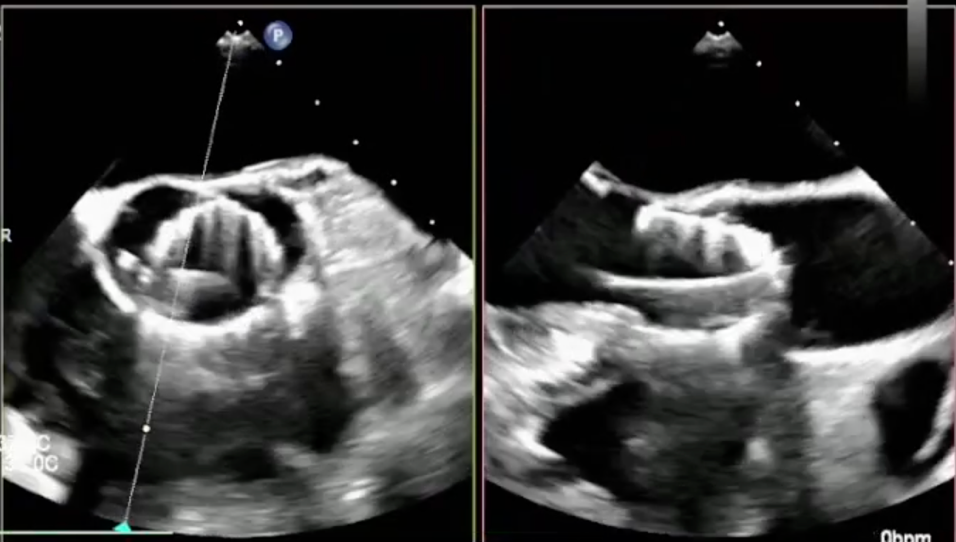

手术直播3:超大左房合并二尖瓣狭窄

本例患者存在严重心衰症状。心脏超声提示其左心房内径显著增大至176mm,属“超大左房”,并伴有重度二尖瓣狭窄,病情极为复杂危重。巨大的左房不仅显著增加了经房间隔穿刺及导管操作的技术难度与风险,也对术者建立稳定轨道、精准输送瓣膜的能力提出了极限挑战。

建立股静脉-房间隔-左房-左室-主动脉轨道

行二尖瓣球囊扩张

成功植入TAVR瓣膜